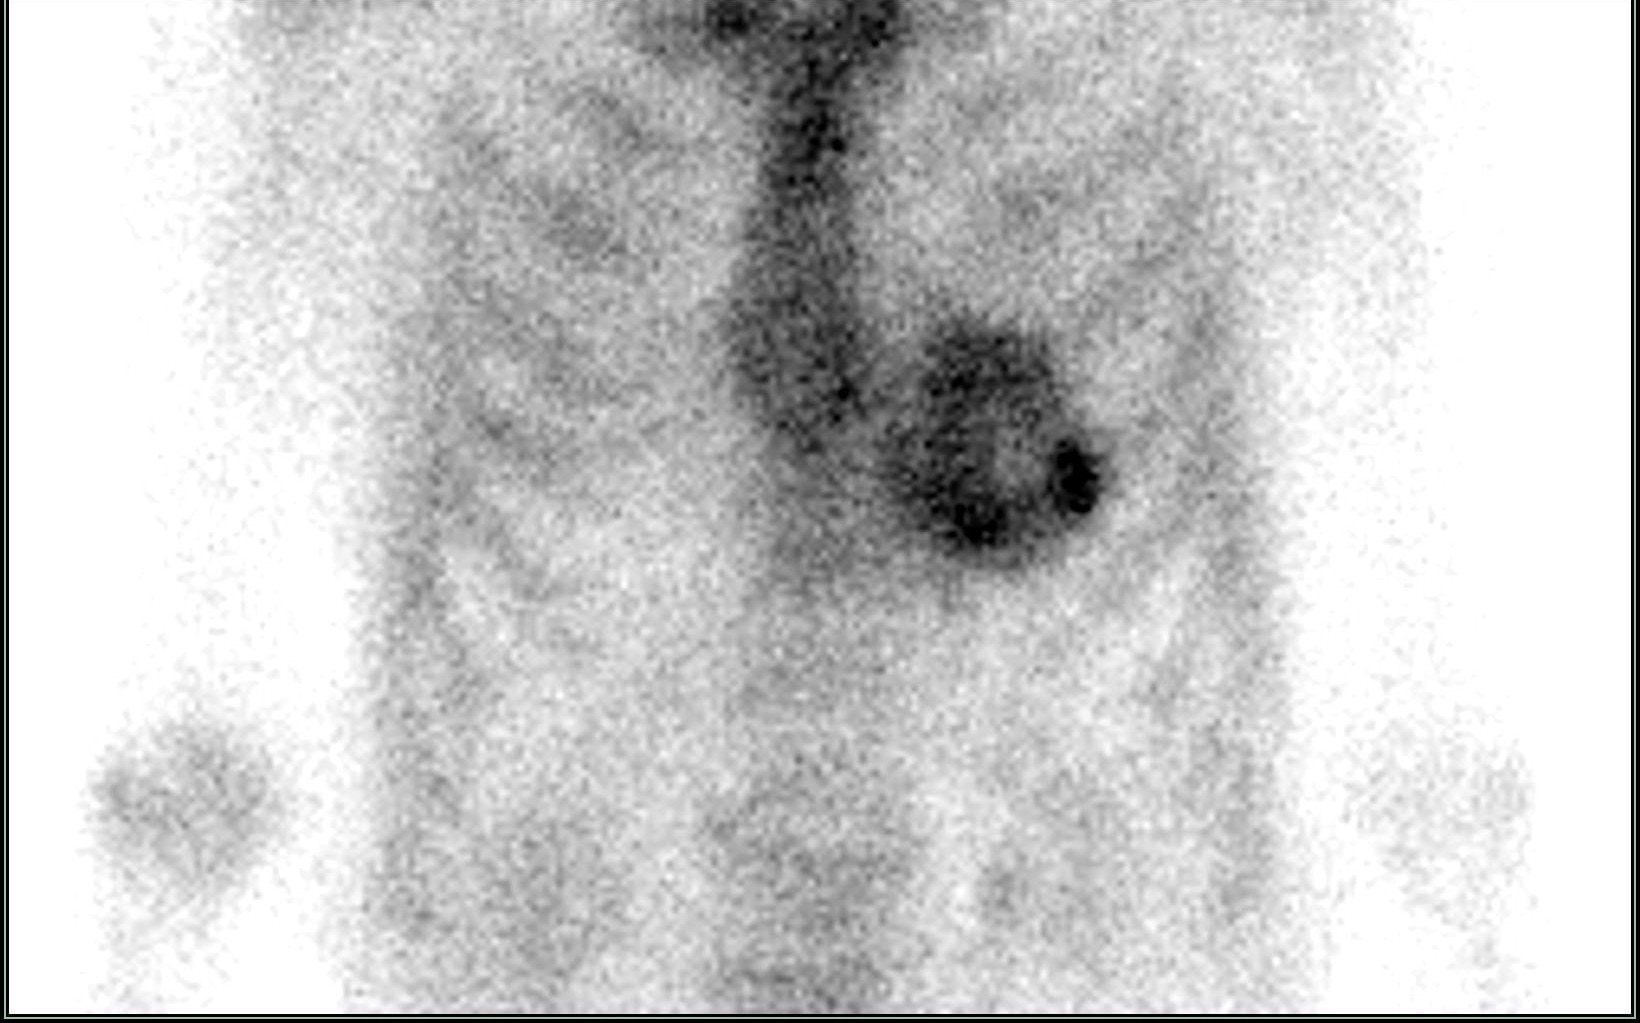

amylo3Tyto látky se vážou na amyloidové fibrily v myokardu a umožňují specifickou detekci TTR amyloidózy. Snímkování se provádí planárně a pomocí SPECT/CT, které poskytuje detailní anatomické a funkční informace.

Hodnocení nálezu

• Grade 0: žádná akumulace v myokardu.

• Grade 1: minimální vychytávání menší než v žebrech.

• Grade 2: akumulace podobná jako v žebrech.

• Grade 3: akumulace vyšší než v žebrech s jasnou vizualizací myokardu.

Významný je rozdíl mezi ATTR a AL amyloidózou:

• ATTR: typicky silná akumulace radiofarmaka.

• AL: většinou negativní nebo jen slabé vychytávání.

Kombinace scintigrafie s negativním imunofixačním vyšetřením séra a moči prakticky umožňuje neinvazivní potvrzení ATTR amyloidózy bez nutnosti biopsie.